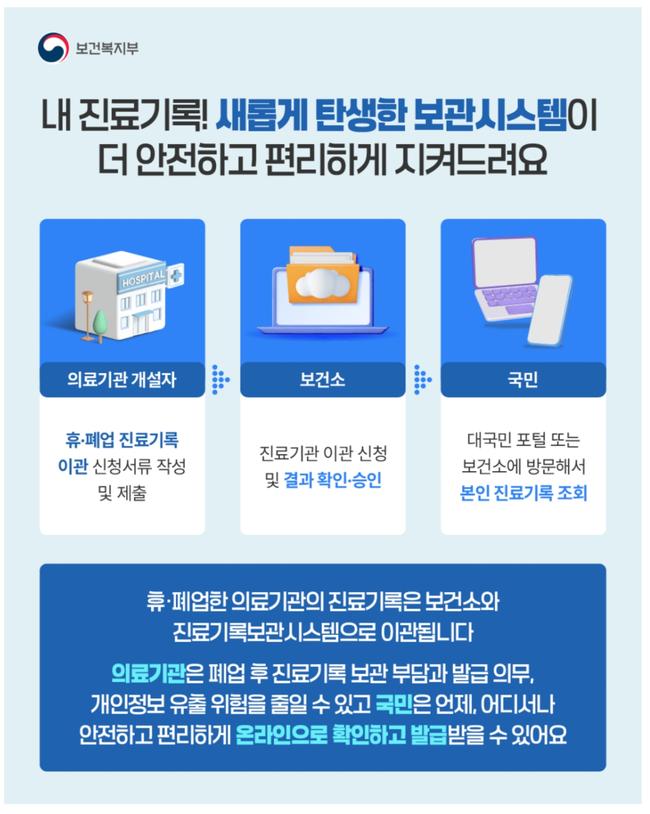

병원 문 닫아도 진료기록 안전하게…보관시스템 전면 개선

병원 문 닫아도 진료기록 안전하게…보관시스템 전면 개선